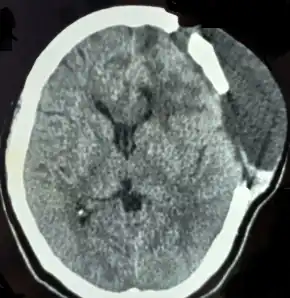

CT scan

Diagnosis of a cerebrospinal fluid leak is performed through a combination of measurement of the CSF pressure and a computed tomography myelogram (CTM) scan of the spinal column for fluid leaks.[15] The opening fluid pressure in the spinal canal is obtained by performing a lumbar puncture, also known as a spinal tap. Once the pressure is measured, a radiocontrast agent is injected into the spinal fluid. The contrast then diffuses out through the dura sac before leaking through dural holes. This allows for a CTM with fluoroscopy to locate and image any sites of dura rupture via contrast seen outside the dura sac in the imagery.[13][25][28]